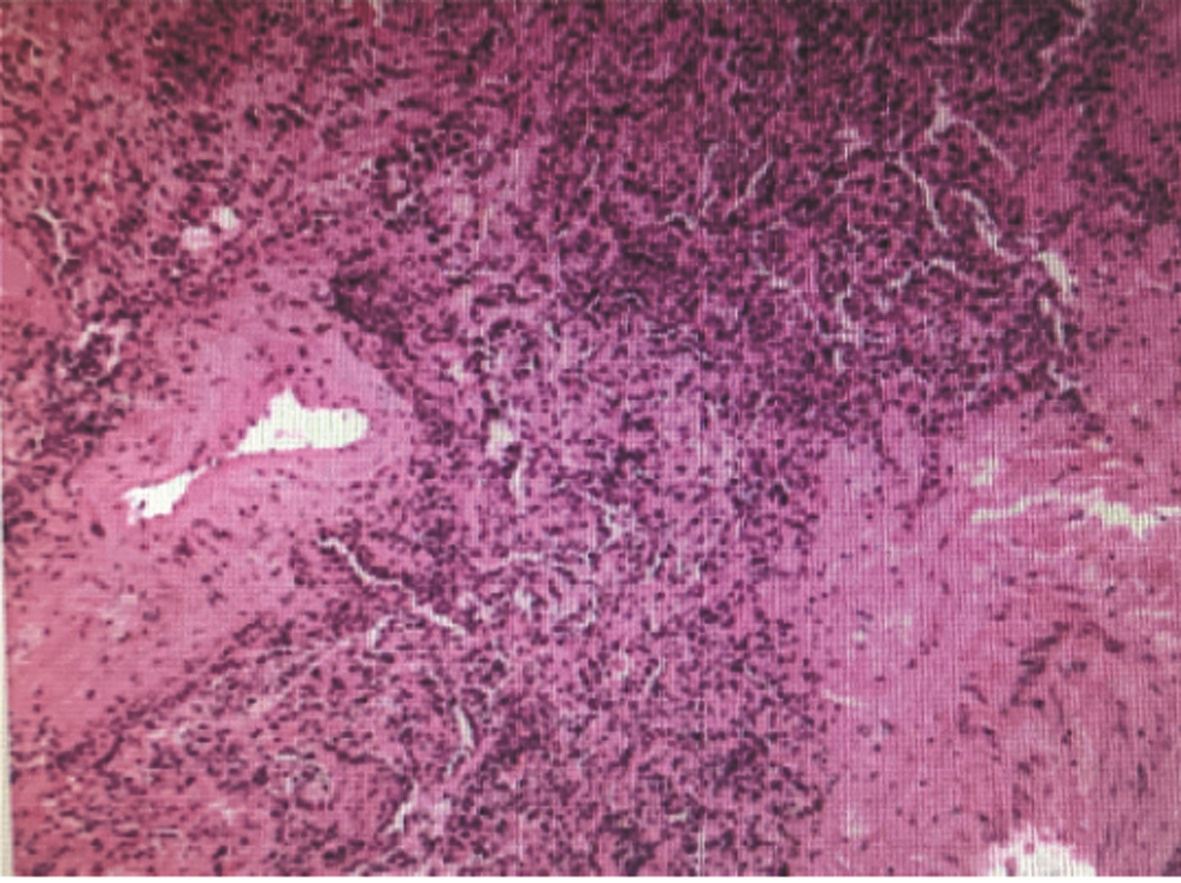

A case of eosinophilia mainly manifesting as liver injury

Hao WU, Xin ZHENG, Lei ZHU, Dong YANG

2022, 38(4): 883-885. DOI: 10.3969/j.issn.1001-5256.2022.04.027

Abstract(2133) HTML (304) PDF (2636KB)(146)

Abstract: